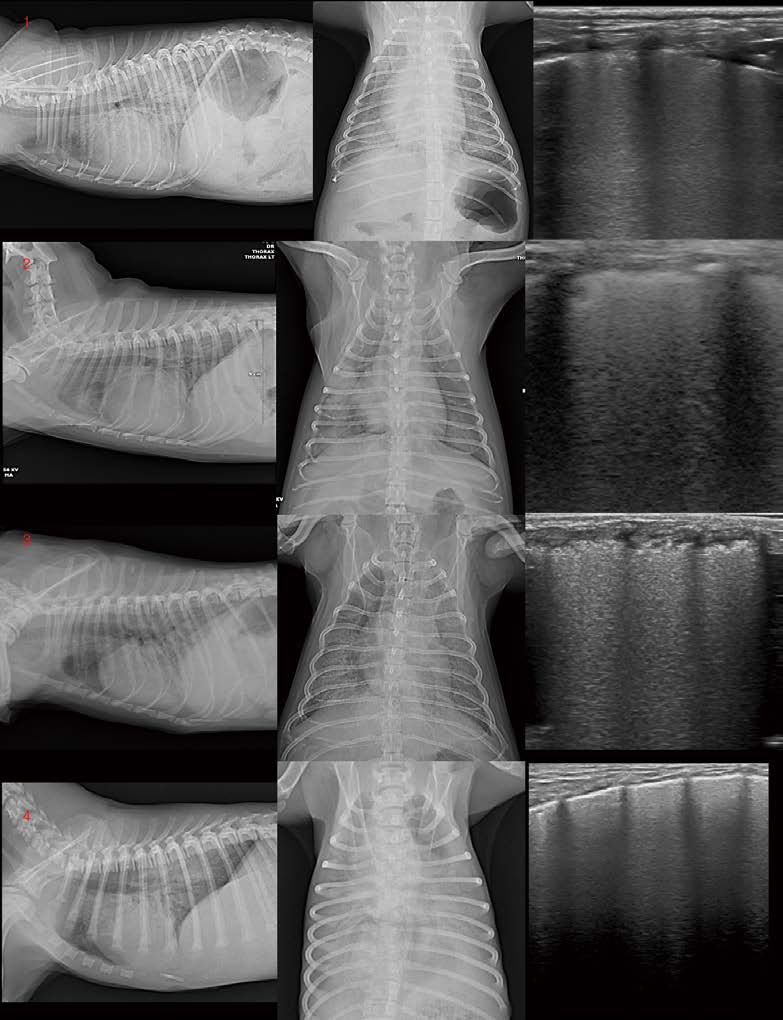

[대한수의사회지 24.png

11살 중성화 수컷 Poodle이 구토, 식욕저하, 기력저하, 기침 증상으로 내원하였습니다. 혈액 검사에서 WBC 72500, CRP 14가 관찰되었습니다. 중성화 수컷임에도 불구하고 복부초음파에서 자궁과 유사한 구조물이 확인되며, pyometra 소견(고에코성의 fluid가 저류된 자궁 확장 및 벽 비후)이 관찰됩니다(A, B). 좌측 자궁각 끝에는 이질적 oval shaped 종괴가 관찰됩니다(C). 바로 수술적 제거를 실시하였고, 좌측 자궁각 끝의 종괴는 testicle로 확인되었으며, 환자는 hermaphrodite(having both male and female tissues)로 진단할 수 있었습니다(D). 환자는 수술 전 구토 증상이 있었는데, 수술 이후 오른쪽 후엽의 밀도가 유의적으로 증가하였습니다(E). 폐초음파에서 전형적인 폐렴 소견(shred sign, dynamic air bronchogram을 보이는 폐침윤 양상)이 관찰됩니다(G). 환자는 aspiration pneumonia 상태로 판단되었으며, 적극적인 응급중환자과 관리를 지속하였습니다. 그러나 2일 뒤 호흡곤란이 심해지고, 좌측 후엽의 밀도 증가 소견이 추가로 관찰됩니다(F). 폐초음파에서 우측 후엽의 폐렴 소견과 달리 좌측 후엽은 confluent B lines with irregular pleural line 소견이 관찰됩니다. Non-cardiogenic pulmonary edema(NCPE) 상태로 생각됩니다. 환자는 안타깝게도 자궁축농증, aspiration pneumonia의 전신 염증성 질환에 이차적으로 NCPE가 발생했을 것으로 생각되며, 개선되지 못하고 3일 후 사망하였습니다.

Aspiration pneumonia는 aspiration 이후 24시간까지도 흉부방사선 검사에서 나타나지 않을 수 있습니다. 이 환자도 술 전 흉부방사선 검사에서 유의적 이상 소견이 관찰되지 않았으나, 수술 이후 우측 후엽의 폐렴 소견이 관찰되었습니다. 또한 Aspiration pneumonia는 초반에 정상 체온, 정상 lung sound, 정상 호흡수를 보일 수 있다고 알려져 있으며, 인지를 못하는 과정에서 빠르게 sepsis, acute respiratory distress syndrome, multiple organ failure까지 진행될 수도 있다고 알려져 있습니다. NCPE의 영상학적 특징을 이 환자에서 잘 관찰할 수 있습니다. NCPE는 흉부방사선 검사에서 central bat-wing pattern(peripheral air sparing)이 관찰될 수 있는데, center쪽에 가까울수록 밀도가 높고, 말초로 갈수록 fade out되는 경향이 있습니다. 이 환자의 흉부방사선 좌측 후엽에서도 전형적인 NCPE의 peripheral air sparing 소견이 관찰됩니다. 또한 NCPE의 폐초음파 검사에서는 cardiogenic pulmonary edema와 비교 시 상대적으로 thickened/uneven pleural line이 관찰될 수 있으며, Inhomogeneous lung tissue with spared area가 관찰될 수 있습니다. 이 환자의 폐초음파 검사에서도 다소 불규칙한 pleural line이 관찰됩니다.

<여기서 잠깐 퀴즈!>

Q. 다음 환자들은 모두 NCPE로 진단된 환자들입니다. 이 중 다행히 잘 회복된 환자는 어떤 환자

일까요?

1번째 환자는 11살 수컷 Y.T가 CKD로 인한 빈혈로 내원하였고, 수혈 이후 transfusion-related acute lung injury가 발생하였습니다. 2번째 환자는 12살 암컷, Shih-Tzu가 구토 증상으로 내원하였고, 심한 췌장염이 확인되었으며, 입원 치료 중 호흡곤란이 발생하였습니다. 3번째 환자는 13살 중성화 수컷 Shih-Tzu가 미용 목욕 후 급성 호흡 곤란을 보였고 입원 3일째 영상입니다. 4번째 환자는 4개월 암컷 Beagle이 보호자로부터 목이 졸린 이후 급성 호흡 곤란을 보여 내원하였습니다. 4 환자 모두, 앞서 설명드린 증례 4. 환자의 NCPE 흉부방사선, 폐초음파 영상학적 패턴과 유사합니다.

정답은 4번 환자입니다.

A. 수혈, 췌장염, aspiration 등의 심각한 염증성 변화에 따른 NCPE 환자들은 모두 회복하지 못했고, 일시적인 압박에 의한 NCPE였던 4번째 환자는 잘 개선되어 퇴원하였습니다.